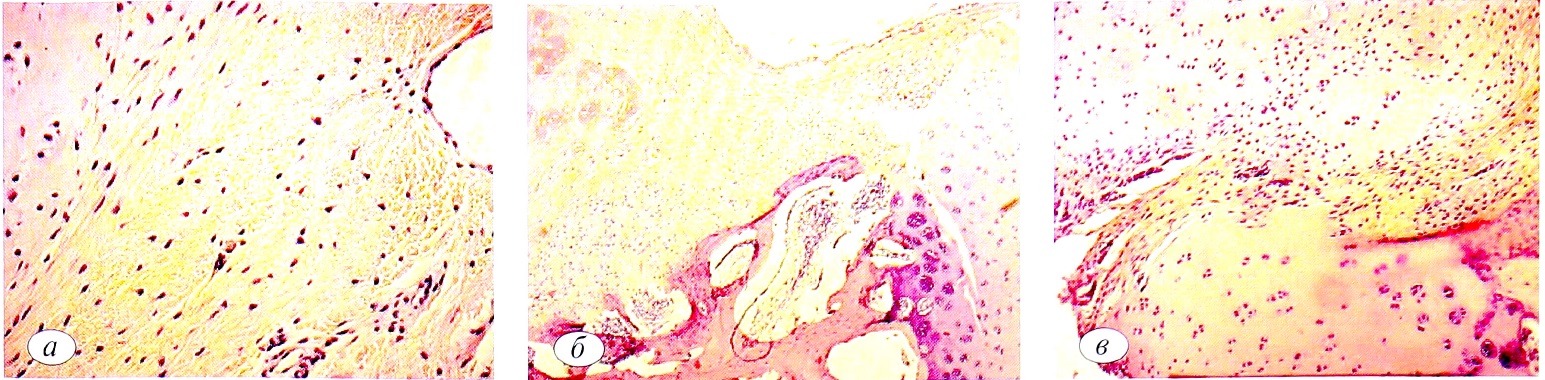

Рис. 3. Динамика макроскопической картины дефекта в 1 -й экспериментальной группе. а — через 1 мес; б— через 3 мес; в—через 6 мес.

Fig. 3. Dynamics of a macroscopic pattern defect in the 1st experimental group. a — after 1 month; б — after 3 months; в — after 6 months.

В 1-й группе к 6 мес наблюдения макроскопически определяли динамику восполнения дефекта в рамках минус-ткань: дно костно-хрящевого дефекта эрозировано, практически не заполнено рубцовой или хрящеподобной тканью, граница между зоной дефекта и здоровым собственным гиалиновым хрящом прослеживается четко (рис. 3, а). Глубина дефекта итогово составляла в среднем 3—6 мм.

Последовательные изменения в микроскопической картине области костно-хрящевого дефекта в 1-й группе животных отражены на рис. 3, б. Аналогично макроскопической картине определяется эффект «минус-ткань», достигающий 50% исходной глубины фрезевого канала. Края дефекта ровные, гладкие; граница между новообразованной тканью и сохраненным гиалиновым суставным хрящом прослеживается четко, так как новообразованная ткань полнокровна.

Удельные объемы тканей в среднем составили: хондроциты — 4,18±0,2%, хрящевой матрикс — 33,73±1,3%, соединительная ткань — 62,09±1,3%; средняя глубина дефекта 56,1±2,1% от толщины нативного хряща.